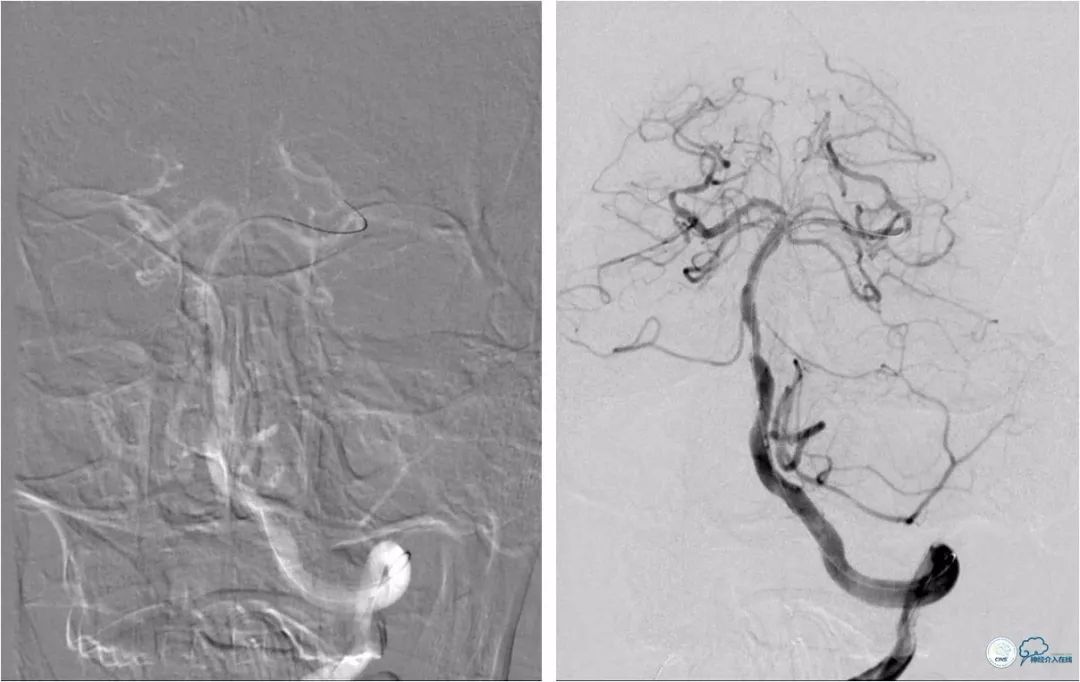

DSA:左椎动脉优势,左椎动脉V1段重度狭窄,右椎动脉V1段中度狭窄,双椎动脉V4-基底动脉下段重度狭窄,狭窄率约为85%,狭窄段有AICA发出,双侧后交通动脉未开放(图6-9)。

图6

图7

图8

图9